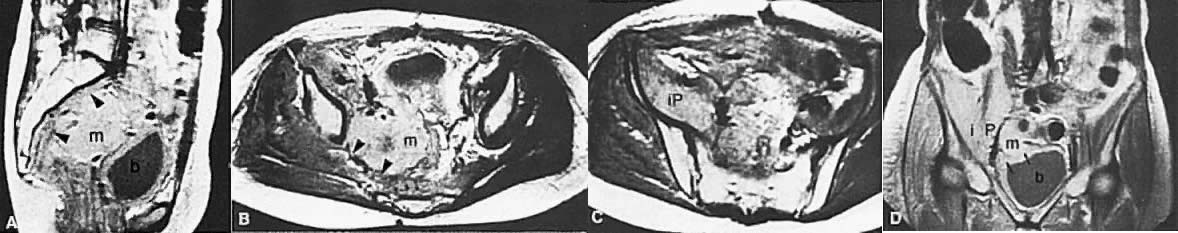

Fig. 17. Recurrent cervical carcinoma with possible radiation changes in the bones and muscles. Sagittal ( A ), low-transverse ( B ), coronal ( C ), and high-transverse ( D) T1-weighted MRI of the pelvis show a large high-signal-intensity mass ( m) (density less than that of fat and more than that of muscle) superior and posterior to the bladder ( b ). Note thickening of the right lateral and superior bladder wall caused by tumor invasion ( arrows ). There is also spread of tumor to the pelvic sidewall ( arrowheads ). There is thickening and increased signal intensity to the right iliopsoas muscle ( ip) compared to the left. There is also evidence of increased signal intensity to the bone marrow of the sacrum and L5 in A. The muscle and bone changes are probably caused by radiation.